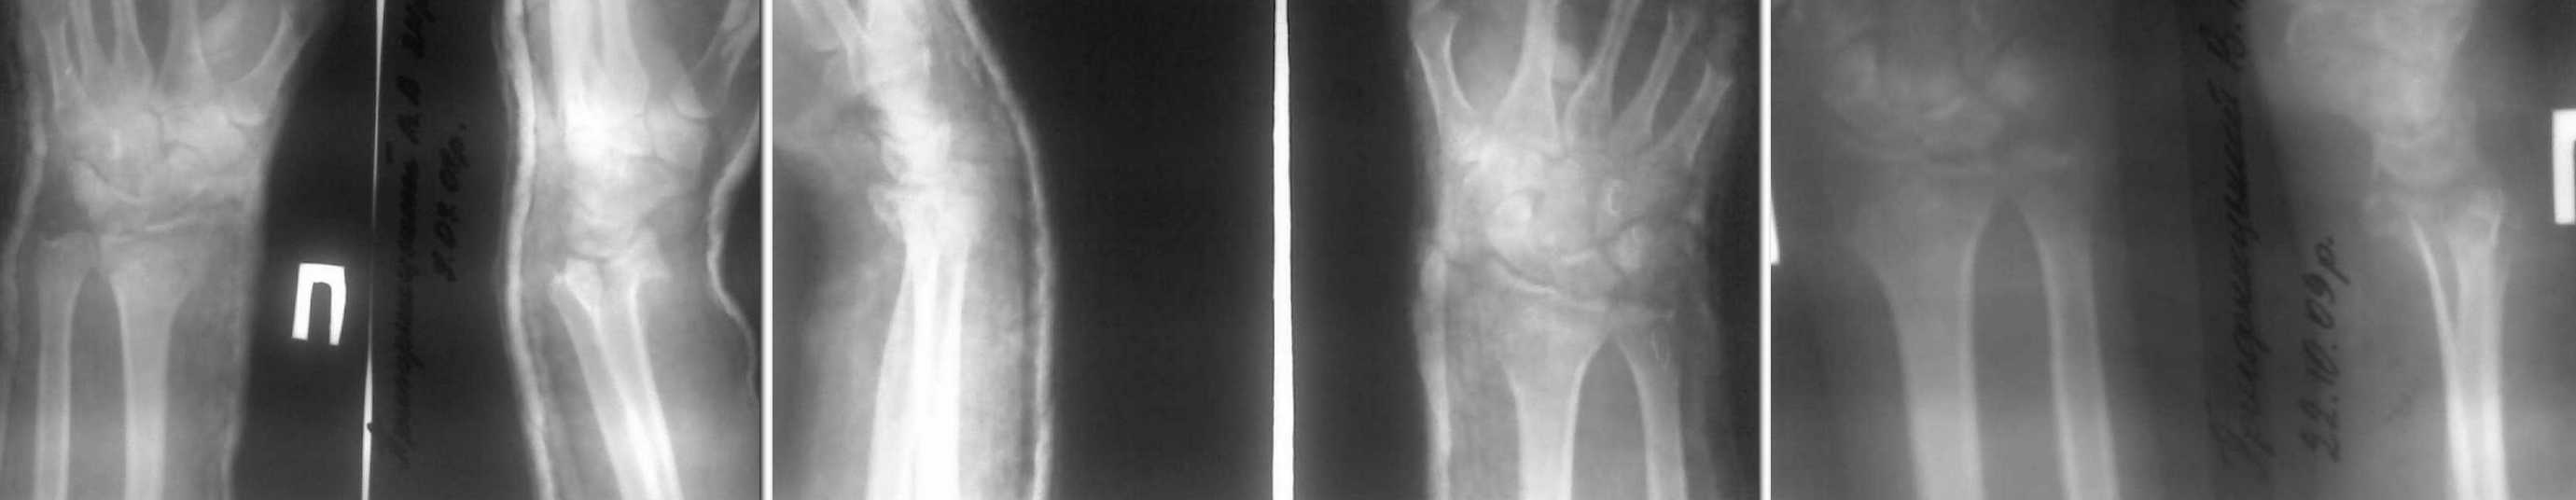

Здравствуйте, уважаемые коллеги.Хотим услышать Ваше мнение по поводу лечения пациента 24 лет с диагнозом неправильно консолидирываный внутрисуставный перелом дистального метаэпифиза правой лучевой кости. Травма 3 мес назад. Была выполнена закрытая репозиция, гипсовая иммобилизация. 2 мес. назад гипсовая повязка снята, и больной начал разрабатывать движения. Сейчас жалобы на боли в лучезапястном суставе, появляющиеся после физической нагрузки, особенно ограничено и болезненно тыльное сгибание, остальные движения ограничены в меньшей степени, слегка болезненны в крайних положениях. Неврологических нарушений клинически нет. Пациент военнослужащий, физического труда.Мы рассматриваем такие варианты: 1. Продолжить разработку движений с физметодами2. оперативное лечение с восстановлением анатомических соотношений в суставе.

Уважаемый Евгений, возможно, полезной для предоперационного планирования может оказаться Ргр здорового лучезапястного сустава, особенно в том случае, если данная операция не является рутинной для Вас. Тогда, отталкиваясь от Ргр здорового сустава, как от идеального шаблона, Вы сможете максимально аргументировано составить предоперационный план, в том числе и определиться с уровнем остеотомии. Так же нашёл у себя в архиве более - менее похожий случай, он во вложенном файле, может что-то окажется полезным для Вас. Пациентка 26 лет, упала с велосипеда. Лечилась консервативно. Обратилась к нам через 3 мес. Ргр на 1ом слайде. При этом достаточно хорошо видна и импрессия хряща. Выполнена остеотомия, зона её открыта, как книга и с помощью импактора возвращены на место вдавленные участки суставной поверхности, при этом суставная поверхность ладьевидной и полулунной костей служили естественным шаблоном для восстановления суставной поверхности лучевой кости. Так как дефект получился достаточно большим и винты пришлось проводить субхондрально, воспользовался Хроносом для пластики, можно было и аутокость применить, естественно. Но ограничился только Хроносом (слайд №2). Сейчас эти пластины я уже не использую, появились более элегантные версии с винтами 2,4 и 2,7 мм и пр. Аппарат в этом случае мне в ходе операции не понадобился, но это скорее исключение, чем правило - *железный ассистент* всегда наготове. Через год с небольшим пластину удалил, слайд №3, здесь же фотогафия зоны бывшего дефекта, замещённого Хроносом. На слайде №4 - Ргр после удаления в сравнении с Ргр здорового лучезапястного сустава, дабы все наши как успехи, так и погрешности и недоработки были отчётливо видны. Восстановление функции полное, на велосипеде катается.

А можно рентгенограммы без гипса и в лучшем качестве? Не совсем понятно, что же там в суставе сейчас творится. Боковую проекцию с выведением суставной щели желательно, сделайте профильный снимок с углом в пятнадцать-двадцать градусов между осью предплечья и плоскостью кассеты. Ну, чтобы видно было, о чём говорить. :-) В спорных случаях можно и КТ не погнушаться.

Последний снимок сделан без гипса, к сожалению качество снимка и качество сканирования дают такую размытую картину. Сделаем такую проекцию и представим снимок, но не раньше понедельника (пациент придёт в понедельник)